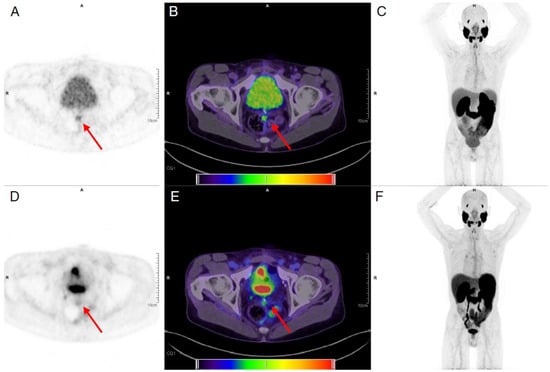

6. Dual Tracer

- Alberts, I.; Schepers, R.; Zeimpekis, K.; Sari, H.; Rominger, A.; Afshar-Oromieh, A. Combined [68 Ga]Ga-PSMA-11 and low-dose 2-[18F]FDG PET/CT using a long-axial field of view scanner for patients referred for [177Lu]-PSMA-radioligand therapy. Eur. J. Nucl. Med. Mol. Imaging 2023, 50, 951–956. [Google Scholar] [CrossRef]

- Van Sluis, J.; Borra, R.; Tsoumpas, C.; van Snick, J.H.; Roya, M.; Ten Hove, D.; Brouwers, A.H.; Lammertsma, A.A.; Noordzij, W.; Dierckx, R.; et al. Extending the clinical capabilities of short- and long-lived positron-emitting radionuclides through high sensitivity PET/CT. Cancer Imaging 2022, 22, 69. [Google Scholar] [CrossRef]

- Liu, G.; Mao, W.; Yu, H.; Hu, Y.; Gu, J.; Shi, H. One-stop [(18)F]FDG and [(68)Ga]Ga-DOTA-FAPI-04 total-body PET/CT examination with dual-low activity: A feasibility study. Eur. J. Nucl. Med. Mol. Imaging 2023, 50, 2271–2281. [Google Scholar] [CrossRef]